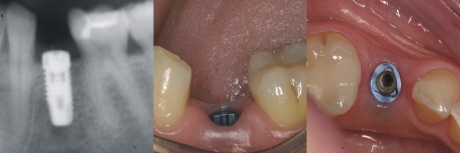

Einphasig oder Zweiphasig?

Einphasige Implantate=einteilige Implantate

Einphasige Implantate bestehen aus einem Stück und werden daher auch einteilige Implantate genannt. Im Gegensatz zu den zweiphasigen (zweiteiligen) Implantaten ist der Aufbau schon direkt ein festes Teil des Implantates und lässt sich nicht abschrauben.

Einteilige Implantate sind dafür konzipiert, dass sie sofort versorgt werden (Sofortversorgung).

Zweiphasige Implantate=zweitige Implantate

Bei den zweiphasigen Implantaten bestehen der Implantatkörper und der Aufbauaus zwei Teilen, die miteinander verschraubt werden. Der Aufbau wird erst nach der Einheilung des Implantates aufgeschraubt, weshalb man auch von zweiteiligen Implantaten redet.